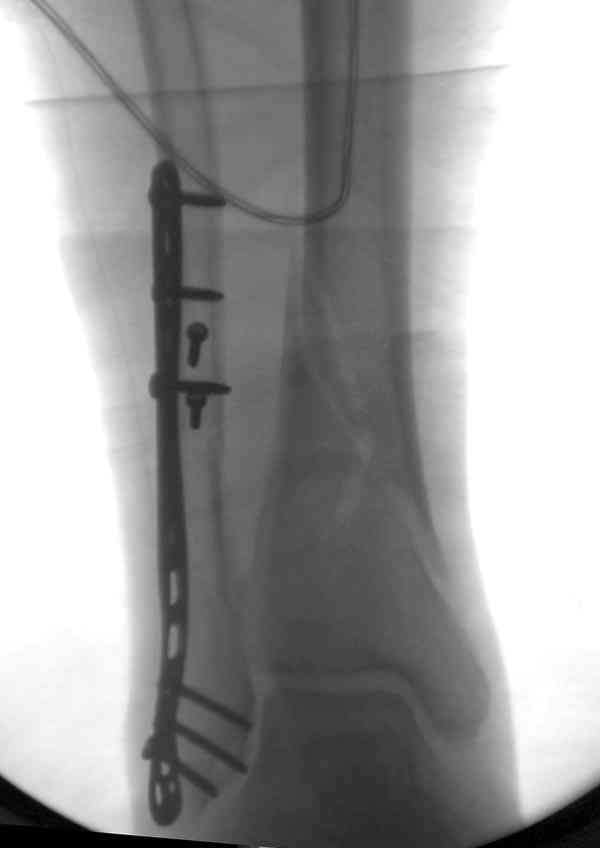

Пару снимков из этапов фиксации: мортизный снимок, техника фиксации

лодыжки, копии из книги

Вложение не в текстовом формате было извлечено…

Имя     : fx technique.jpg

Тип     : image/jpeg

Размер  : 46242 байтов

Описание: отсутствует

Url     : http://weborto.net:8080/pipermail/ortho/attachments/20070817/ae11c0f9/attachment-0004.jpg